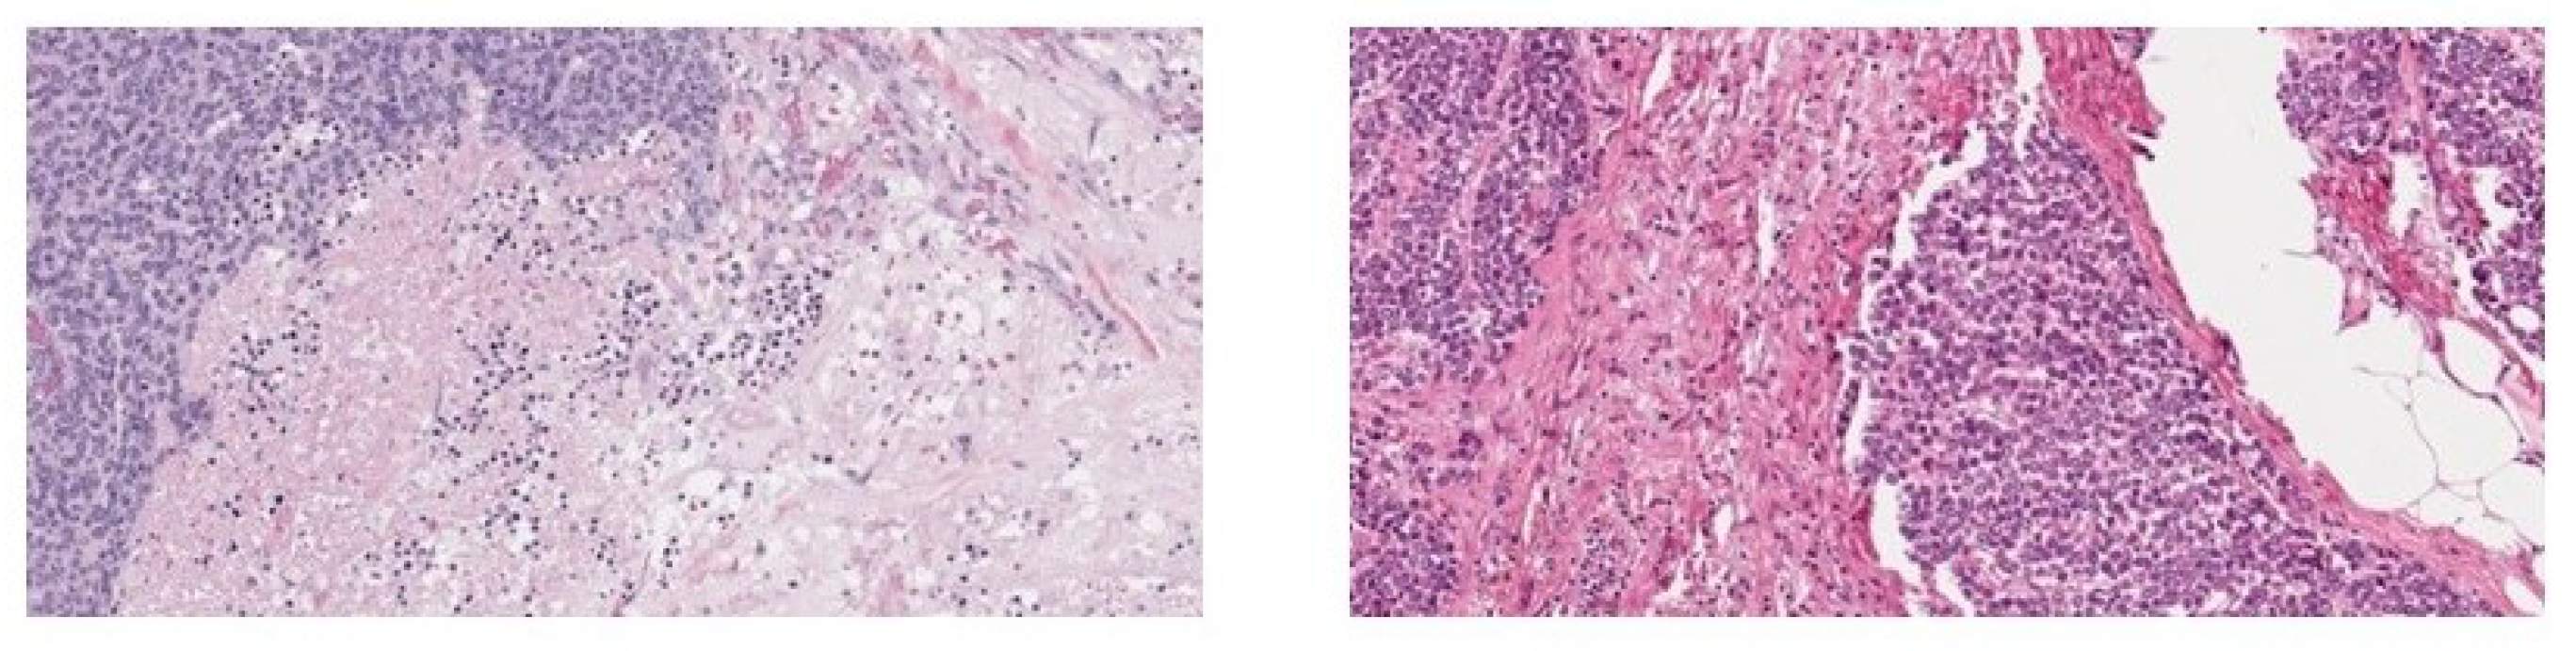

4.1. Dataset Description

| Tissue | Magnifications | Number of Images |

|---|---|---|

| adrenal | , | 50 |

| gland | , | 50 |

| breast | , | 40 |

| colon | , , | 60 |

| prostate | , | 70 |

| Type | Magnifications | Number of Images |

| benign tumor | , , , | 2480 |

| malignant tumor | , , , | 5429 |